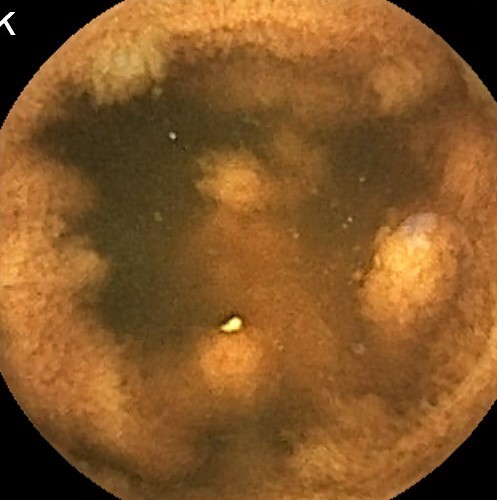

Capsule Endoscopy: Ileum Terminale, Lymphoid Hyperplasia